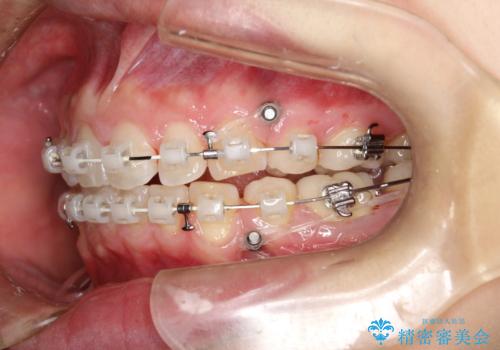

- 矯正装置

- 審美装置

- 治療計画

- 出っ歯を気にして来院されました。

しっかり前歯を下げるために抜歯を合計3本行いワイヤーにて矯正を行う計画としました。